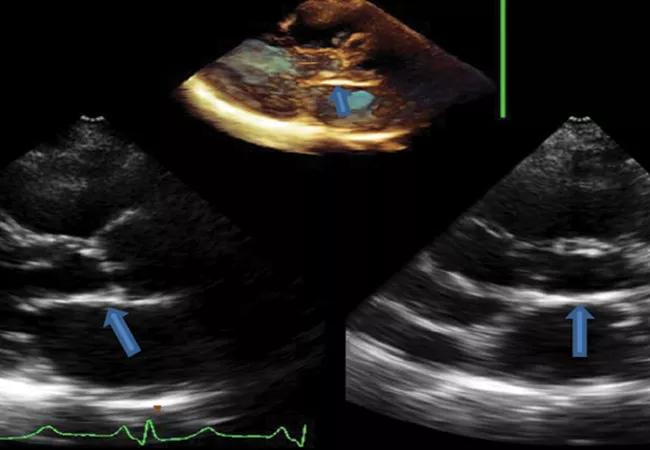

echocardiograms showing heart valve disease

Over a long weekend in early March, Cleveland Clinic will be convening more than two dozen experts in structural heart disease and imaging in Hollywood, Florida, for its 27th Structural Valve Imaging Summit. The summit runs from the evening of Thursday, March 6, to midday Sunday, March 9, 2025, at the Diplomat Beach Resort.